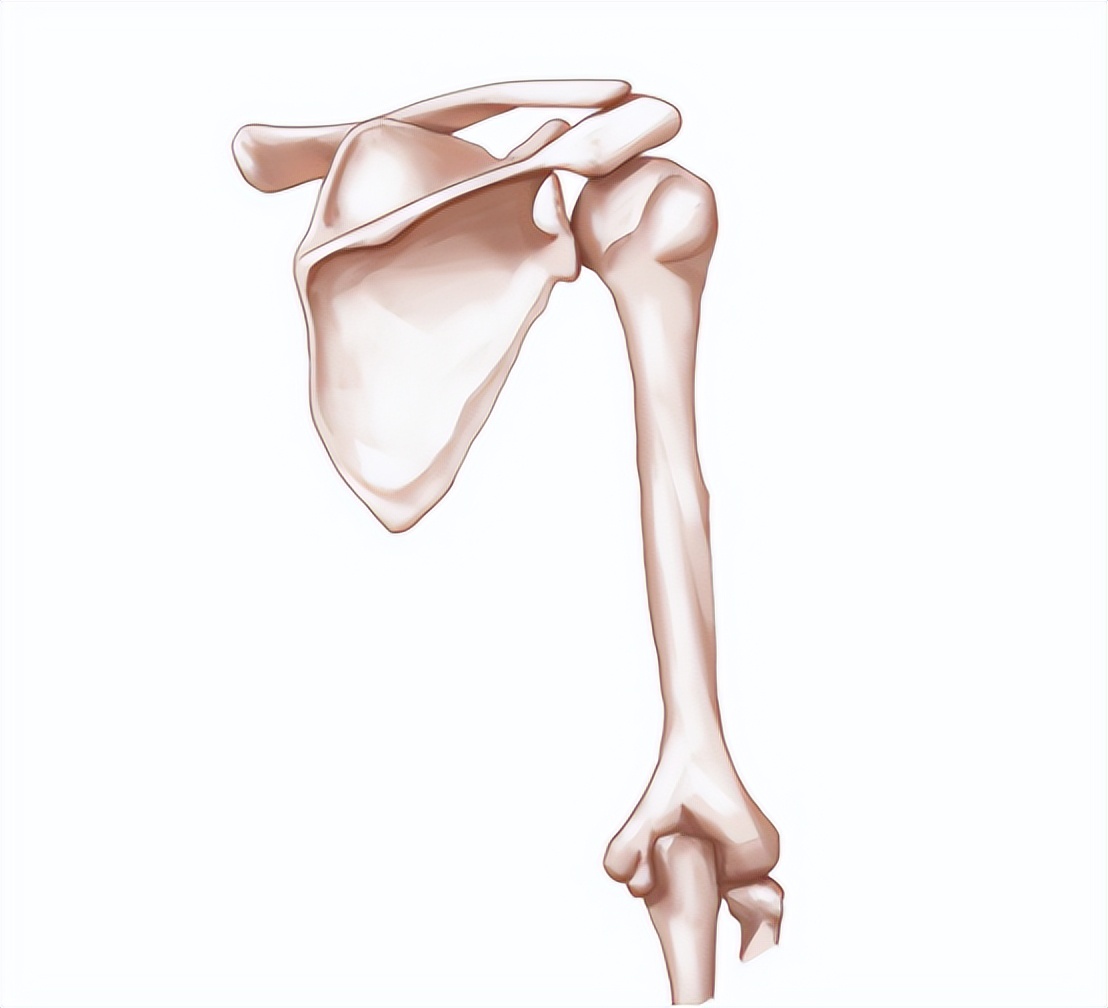

(1)先天性骨骺发育不良: 先天性骨发育不良主要是因为遗传引起,在染色体显性骨病基因遗传给孩子后。 这种基因在儿童软骨发育的时候,会影响软骨细胞成熟、数量和排列。

先天性的骨骼发育不完整时,身体在随着年龄增长变重后会加大骨骼负担。 骨关节在长期承受压力过重后,造成过度磨损与破坏,容易出现骨关节炎。

(2) 创伤:当人体出现坠崖、撞击等事故的时候造成骨关节内骨折、 软骨损坏、截肢后单侧肢体承重、关节内异物存留等问题。

骨关节在恢复的过程中会出现关节面不平整或者有异常的磨损和破坏。 造成积累性损伤出现骨关节炎等疾病。